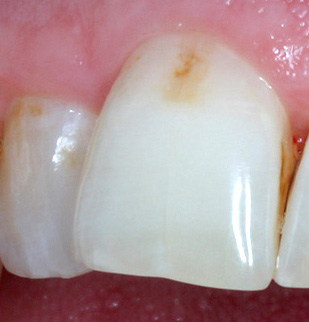

Nella maggior parte dei casi, il paziente non può riconoscere la carie dello smalto nelle prime fasi, poiché la clinica di questa patologia è scarsamente espressa. Quando appare un punto bianco o pigmentato, molti lo attribuiscono alla placca o al tartaro, non capendo la gravità del problema.

Il colore dello smalto interessato può essere diverso, a seconda delle caratteristiche del cibo assunto regolarmente e della presenza di alcuni coloranti in esso.

Nella foto sotto, la carie di smalto è presentata come la fase iniziale della lesione con segni caratteristici di questa particolare fase: